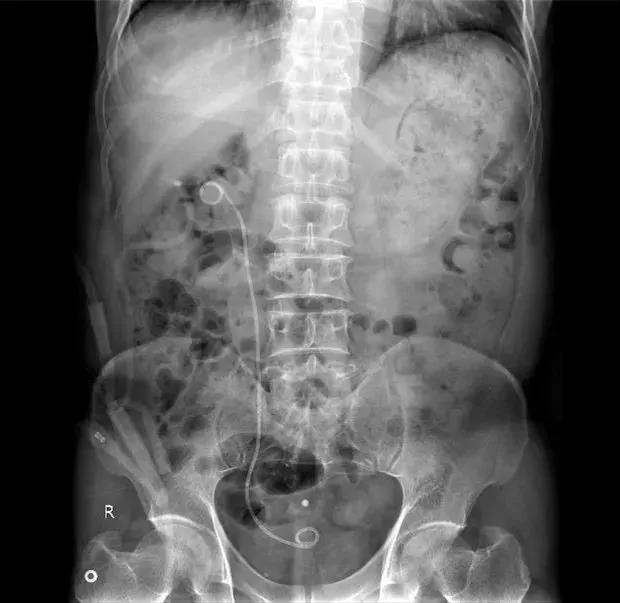

2019年7月在我院行输尿管软镜下右肾结石钬激光碎石术+右侧双J管置入术。

2019年9月在我院行输尿管肾结石钬激光碎石术(2期)+右侧双J管置入术。

2019年10月在我院行输尿管软镜下右肾结石+右输尿管上段多发结石钬激光碎石取石术+右侧双J管置入术。

2019年12月在我院行输尿管软镜下右肾结石+右输尿管上段多发结石钬激光碎石取石术+右侧双J管置入(如术中有残余结石入肾需要ESWL等方式治疗)。